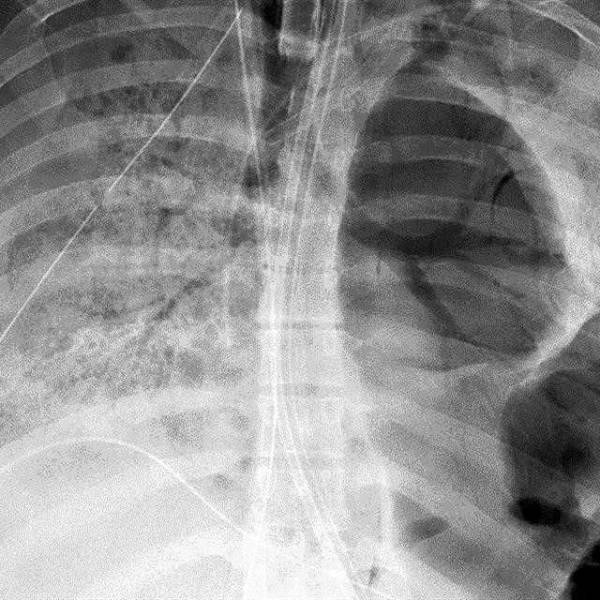

Pero nueve de los 11 pacientes de la UCI de COVID que Reynolds evaluó inicialmente tenían un estudio de burbujas positivo, dijo a MedPage Today.

¿Es posible que todas estas burbujas pasen por los pulmones?  El tránsito de las burbujas sugirió vasodilatación de los capilares pulmonares, dijo Poor. Eso podría significar que la sangre puede fluir demasiado rápido a través de esos capilares para absorber suficiente oxígeno.

Reynolds y Poor prepararon un segundo estudio con otros 18 pacientes de COVID-19 en cuidados intensivos y hallaron que 15 tenían micro burbujas: habían pasado de largo de los pulmones, mediante los capilares dilatados, hasta el cerebro. No hicieron estudios adicionales para descartar que tuvieran el foramen oval de Botal porque la proporción era tan masiva que no se correspondía con la incidencia de ese defecto cardíaco, que afecta a un 20% de la población en general.

El estudio también mostró la razón por la cual las microburbujas obstaculizaban la oxigenación: su cantidad se correlacionaba de manera inversa con la unidad de medida que se usa para saber cuánto oxígeno hay en sangre, el cociente entre la parcial de oxígeno arterial (PaO2) y la fracción de oxígeno inspirada (FiO2). Cuando está por debajo de 200 mililitros, hay hipoxemia. Es lo que se veía en los pacientes estudiados.

A mayor abundancia de microburbujas, también se veía una peor función respiratoria, con lo cual se las asoció al endurecimiento de los pulmones.